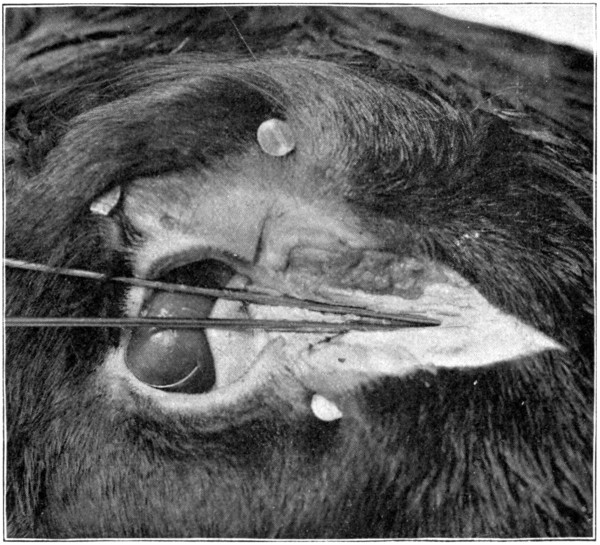

Fig. 47—Showing method of making the initial cuts in the skin. (Page 97.)

Fig. 48—Part of calf’s head, showing the first cut to be made in the bones of the orbit. (Page 102.)

Fig. 49—Showing all the cuts to be made through the bones of the orbit. (Page 102.)

Using the left orbit, begin the dissection by

making an incision directly over the supra-orbital

ridge, extending from over the inner

to the outer canthus. At the middle of that line,

make an incision, and cut at right angles upward

to the top of the head. Next make a cut

below the eye, extending from the outer to

the inner canthus. (Fig. 47.) Loosen the

skin[98-

99]

from the bone with the scalpel, and lay bare

the skull immediately over the orbit. Fold the

flaps of the skin back and fasten them down

to the skull with pins or tacks so they will not

interfere with the work.

Fig. 50—Showing how to pry the cut bone loose. (Page 102.)

Fig. 51—“In removing orbital contents dissect close to the bone.”

Fig. 52—Showing excavated orbit. (Page 105.)

Using the hammer and the chisel, cut[100]

through the roof of the orbit at the middle of

the supra-orbital ridge, and continue upward

for about two and one-half inches. Do not

strike hard blows, or the chisel may be driven

through the underlying tissues. Listen for

the peculiar sound that is heard when the

bone has been completely penetrated; then remove

the chisel. Continue until the full distance

of two and one-half inches of bone has[101-

102]

been separated. (Fig. 48.) Now, begin at the

upper end, and cut through the bone downward

to the right for about two inches toward the

outer canthus. A similar line should be cut

on the right of the centre line toward the inner

canthus. This will mark out two irregular,

triangular-shaped pieces of bone. (Fig. 49.)

Remove the piece on the right-hand side by

prying it off. (Fig. 50.) The left-hand piece

should be pried loose and then carefully cut

away with the scalpel, so that the pulley through[103]

which the superior oblique muscle runs its

tendon, will not be injured. In removing the

orbital contents, dissect close to the bone (Fig.

51), so that the periosteum will also be removed,

and form a sort of sac or capsule in

which will be contained the eye with all its

extrinsic tissues. If difficulty is experienced

in getting at the posterior parts of the orbit,

it will be best to cut away as much more of

the obstructing bone as is necessary. In this

way the “capsule” containing the eye, its six[104-

105]

muscles, the lacrimal gland, and both eyelids,

all in situ, will be removed. (Fig. 54.) As the

orbital entrance of the optic nerve is neared,

care must be exercised not to cut into this

“capsule,” or sever any of the muscles. (Fig.

52 shows the excavated orbit. Fig. 53 shows

an anterior view of the enucleated eye. Fig. 54

is a side view of the enucleated eye.)